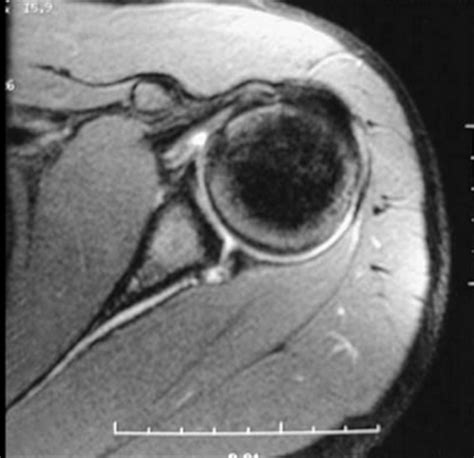

An MRI is a non-invasive imaging technique that uses magnetic fields and radio waves to produce detailed images of the body’s internal structures. For diagnosing a Slap Tear MRI, the scan provides high-resolution images of the shoulder joint, allowing radiologists to identify tears in the labrum and other soft tissue injuries.

Slap Tear MRI scans are particularly useful for diagnosing SLAP tears because they provide clear images of the labrum and surrounding structures. However, interpreting the results requires expertise, as SLAP tears can be subtle and easily missed.

Interpreting the results of a Slap Tear MRI involves a thorough examination of the images by a radiologist. Key findings that indicate a SLAP tear include:

• Abnormal signal intensity within the labrum, suggesting a tear.

• Displacement or detachment of the labrum from the glenoid.

• Fluid or contrast agent extending into the tear, highlighting the extent of the injury.

• Associated injuries, such as rotator cuff tears or biceps tendon pathology.

Radiologists use specific criteria to classify SLAP tears based on their appearance on MRI images. For example, a Type II SLAP tear may show detachment of the labrum and biceps tendon from the glenoid, while a Type IV tear may exhibit a displaced flap of tissue.